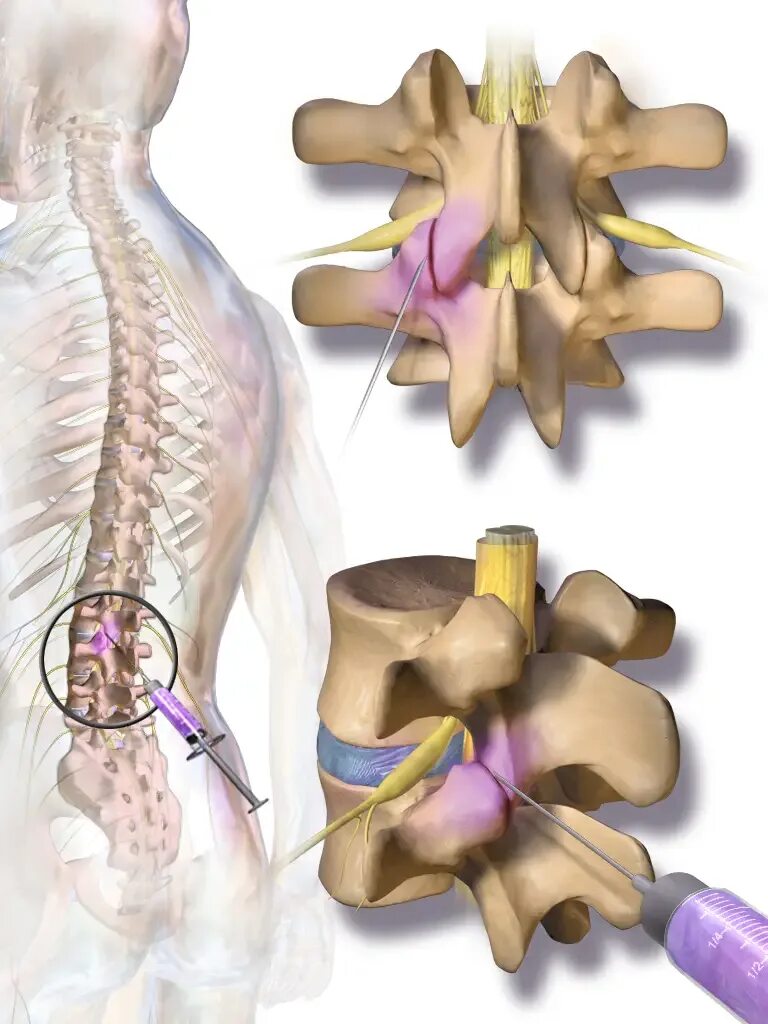

Артроз фасеточных суставов позвоночника